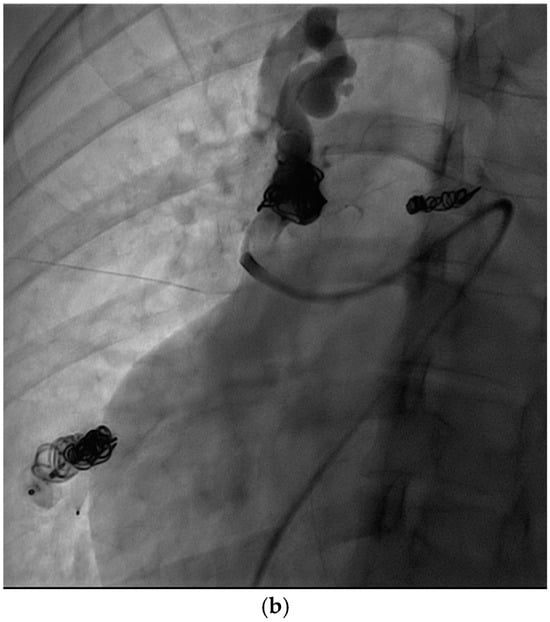

Figure 3.

An 18-year-old male with HHT with a diffuse RLL PAVM with at least four feeding arteries previously embolized. Now presents with recurrence identified on surveillance CT. (a,b) CT of the chest, MIP saggital view, demonstrates multiple collateral pulmonary branches feeding a common outflow channel. (c) Angiogram of the right pulmonary artery, early arterial phase, shows multiple collateral arteries feeding the venous outflow, (d) seen more clearly on the late arterial phase. (e) Repeat angiogram of the right pulmonary artery after embolizing multiple feeding arteries and central venous outflow shows complete occlusion of the RLL PAVM.

These criteria were confirmed angiographically, with criteria 1 demonstrated angiographically as recanalization (Figure 2a,b). Criteria 2, combines accessory feeding arteries and pulmonary collaterals together as they are generally difficult to differentiate angiographically (Figure 3a,b). Criteria 3 is angiographically shown as perfusion of the PAVM outflow via injection of systemic arteries (Figure 4a,b).

The proposed reintervention criteria were based off the greater than 30 years of experiences at a single large HHT center of excellence. The reintervention criteria described in this paper may be used as general guidelines but may not always be generalized to each patient and practice. Additionally, as the population in this study only included adults, it may not be applicable to the pediatric population. The first indication of reintervention requires experience evaluating the embolic devices. A contrast-enhanced chest CT must be windowed in such a way to see the degree to which contrast flows through the embolic device(s). If a column of contrast is measured to be approximately greater than 2–3 mm through, this would suggest a need for reintervention (Figure 2a,b). This may be difficult to determine, and evaluation of the scout images can be helpful to see how well the coil is packed. The second indication for reintervention involves the treatment of accessory pulmonary collaterals (Figure 3a–e). Accessory pulmonary collaterals are a result of adjacent pulmonary vessels which fill the feeding artery or sac beyond the embolic device(s). When this collateral vessel is greater than 2–3 mm, reintervention is indicated. The third criteria involve the treatment of systemic collaterals (Figure 4a–c). This is by far the most complicated issue to address and was the cause of the sole case of iatrogenic stroke. Luckily these systemic collaterals are rare, with a lifetime prevalence of 1.0% [13]. The author’s institutions experience treating these systemic collaterals was previously published. Patients with previously treated PAVMs presenting with hemoptysis are often due to systemic collaterals. In some cases, these lesions can be clearly identified on a chest CTA; however, this is not always the case and therefore a clinical presentation of hemoptysis is enough to indicate reintervention and interrogation of the systemic arteries. Understanding the best way to treat these lesions is an ongoing process.